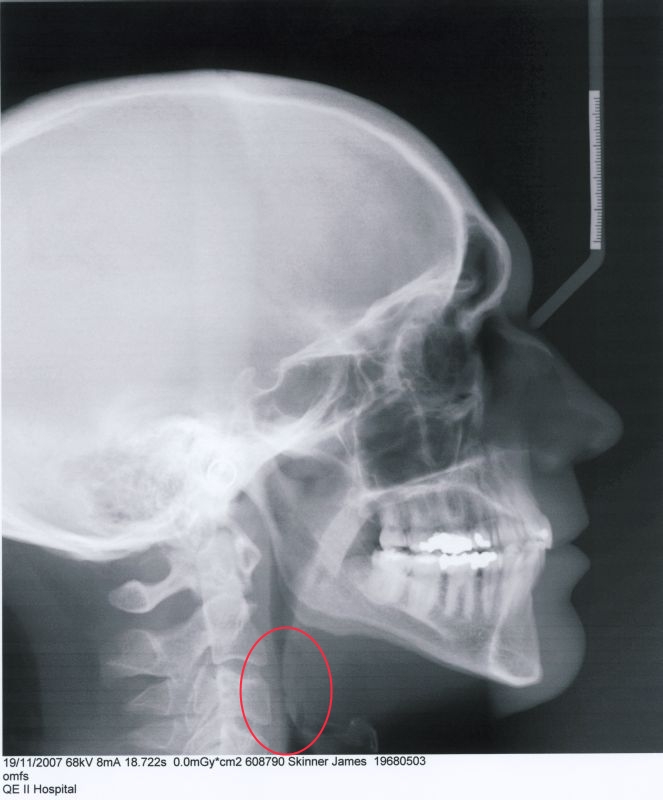

I first began experiencing nasal issues around the year 2000, when I developed allergies. In early 2007, something shifted suddenly. Over the span of just a day or two, I developed severe nasal inflammation. This became a serious problem, as I was already struggling to breathe due to a narrow hypopharyngeal airway.

n 2009, a local ENT recommended turbinate surgery to treat the inflammation—without first investigating the underlying cause. Because of long wait times in my home province of Nova Scotia, I traveled to see a well-known nasal surgeon in Cleveland, Ohio. He performed two surgeries. The first involved correcting a septal spur and reducing my inferior turbinates using radiofrequency (RF). The second, due to concerns about overuse of RF, was a submucosal resection. After the second procedure, he told me he had reduced the turbinates as much as was safely possible—and warned that any further surgery could cause permanent damage.